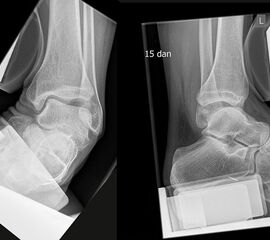

Röntgenaufnahmen dienen vor allem zum Ausschluss einer knöchernen Verletzung und umfassen Aufnahmen des Sprunggelenks anterior-posterior, lateral und 20° Innenrotation (Mortise view). Die über viele Jahre empfohlenen gehaltenen Aufnahmen haben ihre Bedeutung bei der Akutverletzung vollständig verloren, da sie die Behandlungsstrategie nicht beeinflussen (Abb. 2). Bei einer chronischen Instabilität liefen gehaltene Aufnahmen zusätzliche Informationen, wobei auch hier falsch negative Befunde möglich sind 26. Die höchste Zuverlässigkeit liefert die dynamische Untersuchung in Narkose 27

Mithilfe von Ultraschall (siehe auch „Sonographische Diagnostik an Sprunggelenk und Fuß“) lässt sich in der dynamischen Untersuchung eine Instabilität nachweisen 28. Ein Kalibersprung des Bandes sowie ein von Flüssigkeit umspülter Bandstumpf sind weitere sonographische Zeichen einer Bandruptur (Abb.3). Das Untersuchungsverfahren kann bei medialen Instabilitäten ebenso eingesetzt werden wie bei der lateralen Instabilität 29. Auch zum Ausschluss von Syndesmosenverletzungen hat die dynamische Ultraschalluntersuchung eine sehr hohe Sensitivität und Spezifität 30. Beurteilt wird in Höhe der Syndesmose die Translation der Fibula gegenüber der Tibia im Seitenvergleich.

Schnittbildverfahren sind immer dann indiziert, wenn der Verdacht auf Begleitverletzungen besteht, das Schmerzniveau inadäquat hoch ist, oder die akuten Beschwerden innerhalb einer Woche nicht weitgehend abgeklungen sind 31 (Abb. 4-6).